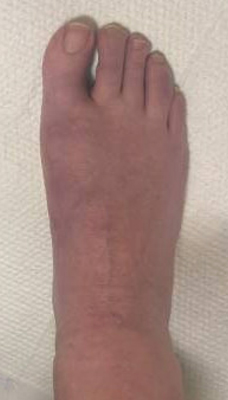

TOTAL ANKLE REPLACEMENT :: ORIF CALCANEUS :: ORIF ANKLE FRACTURE DISLOCATION :: COMPLEX BUNION AND LESSER TOE CORRECTION :: TALUS FRACTURE -1 :: TALUS FRACTURE -2 :: LISFRANC REPAIR :: COMPLEX TRIPLE ARTHRODESIS 1 :: COMPLEX TRIPLE ARTHRODESIS 2 :: MINIMALLY INVASIVE BUNION REPAIR 1 :: MINIMALLY INVASIVE BUNION REPAIR 2 :: ARTHROSCOPIC CARTILAGE REPAIR :: TENEX SPUR DEBRIDEMENT :: Haglunds Debridement and Achilles Repair